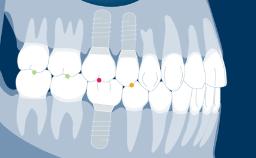

Several factors play a role in making the correct decision. These involve the location of the implant anterior or posterior site, the number of implants, the need to shape tissue, as is often seen with adjacent implants in the anterior area, and the need for occlusal support.

- identify the indications for an implant-supported provisional prosthesis

- select the appropriate type of provisional prosthesis